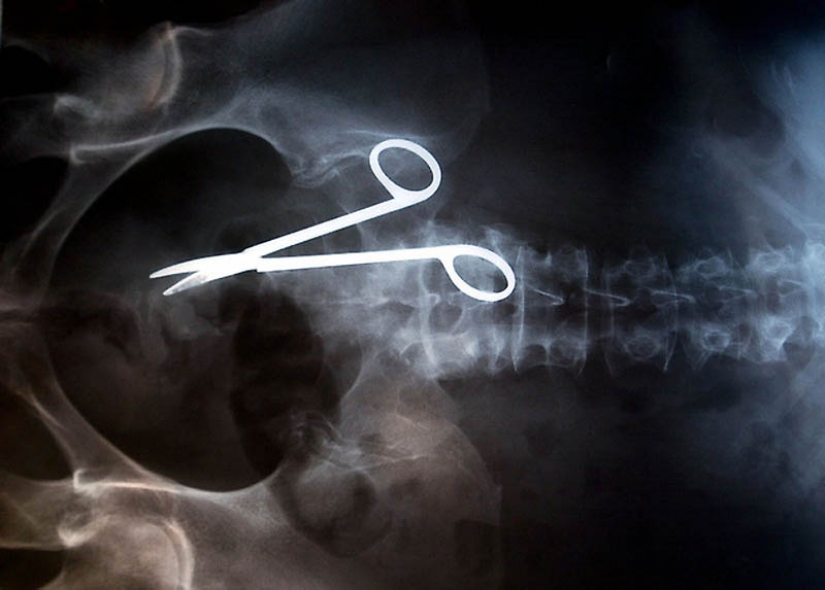

12. Surgical scissors, accidentally forgotten in the body of the patient after surgery. The scissors were discovered only 18 months after the operation, because the woman complained of constant pain in the intestine.